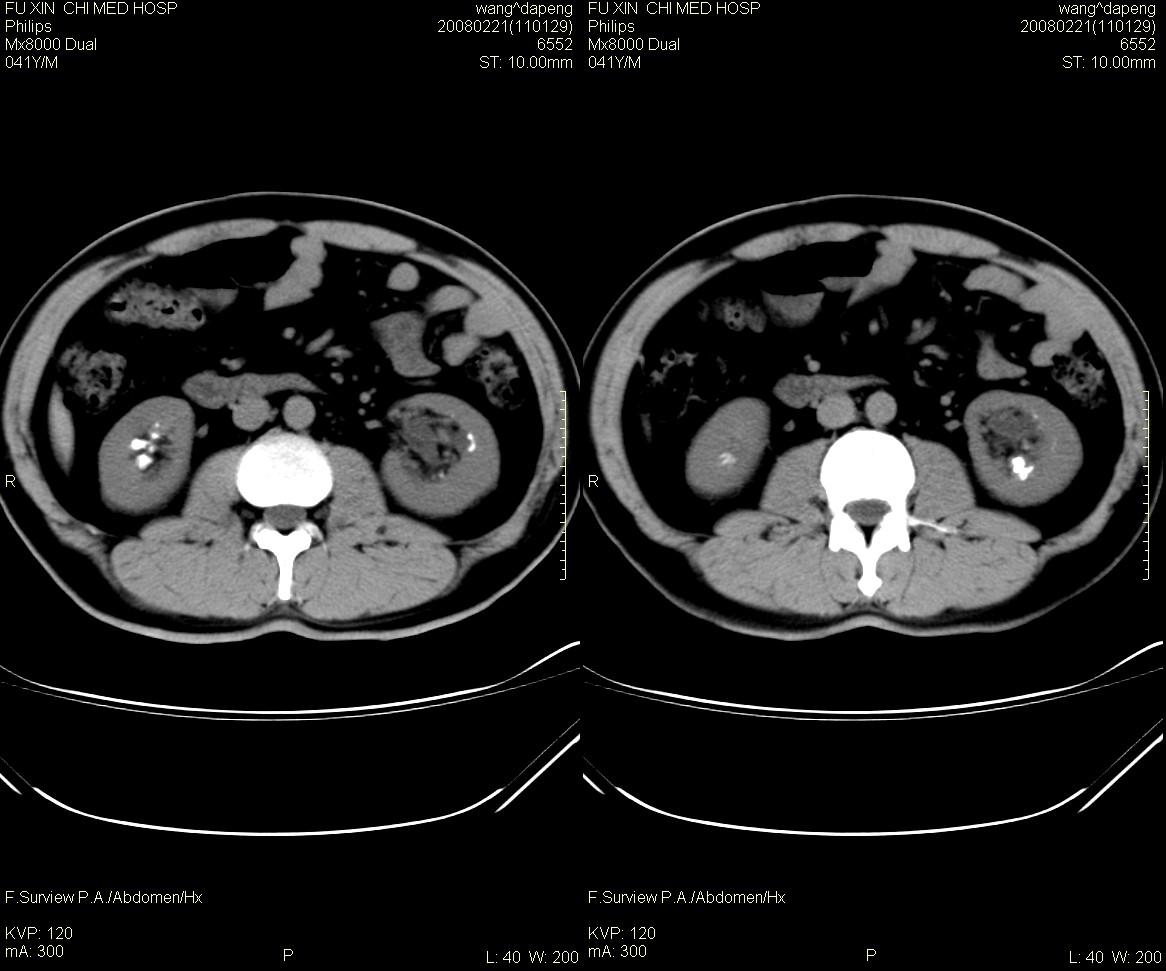

男,41岁,临床发现双肾结石10年。是髓质海绵肾吗?如何确诊。请战友指教。

髓质海绵肾是一种先天性的肾髓质囊性病变, 其特征为肾锥体部乳头管及集合管呈梭形或囊状扩张,并伴发感染和尿路结石形成。在肾标本切面上, 可见髓质中呈海绵状改变。ct平扫表现为肾盏旁锥体内多发小斑点状结石, 成扇形排列.增强扫描后扩张的肾集合管内结石周围有造影剂充盈, 无结石的肾锥体集合管呈条纹状或小囊状造影剂积聚,肾功能正常.

本例支持:髓质海绵肾

海绵肾是先天性的,可能是有遗传倾向的良性肾髓质囊性病变,常于40岁以后发现,易误诊断肾结石和尿路感染。其病理特征是肾小管远端集合小管扩张,形成小囊和囊性空腔,并位于肾盏连接处,易导致结石、感染等。病变一般为双侧性80%的病人部分或全部肾乳头受累。临床上病变局限,轻微者可无明显症状,常见的症状为腰痛、血尿、尿路感染及肾绞痛等。

海绵肾的影像诊断主要靠静脉尿路造影,在平片上表现为双侧肾盏处侧有多发的小结石影。造影后显示肾乳头囊状扩张,内见单发或多发的钙化点,表现为环绕于肾盏、肾盂周围的多数囊腔,形似菜花。ct对海绵肾集合小管囊状扩张的空间分辨率不如ivu高,但对检出其中的小结石较x线敏感。因此,可疑海绵肾的影像诊断应结合上述两种检查。